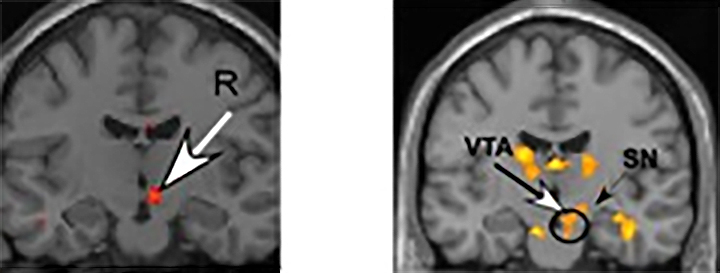

«Мы обнаружили много очень явных сходств между теми, кто был влюблен в течение долгого времени, и теми, кто только что безумно влюбился», — говорит доктор Артур Арон (Arthur Aron), автор исследования, имея в виду активность вентрального отдела (VTA), ключевой области вознаграждения и мотивации мозга, богатой дофамином. — «В этом последнем исследовании VTA показала большую реакцию на изображения давнего партнера по сравнению с изображениями близкого друга или любыми другими изображениями лица».

Рис. Функциональная магнитно-резонансная томография (фМРТ), показывающая активацию мозга людей, недавно влюбившихся (слева), по сравнению с людьми, состоящими в длительном браке и все еще влюбленными (справа). Она показывает аналогичную нейронную активность в вентральной области коры (VTA) мозга. Люди, состоящие в браке в течение длительного времени, также демонстрируют значительную нейронную активацию в богатых дофамином областях вознаграждения SN в ответ на образы своего партнера.

Другими словами, у некоторых представителей пожилых пар при виде фотографий партнера в мозгу происходят точно такие же химические реакции, что и у людей, находящихся на ранних стадиях влюбленности.